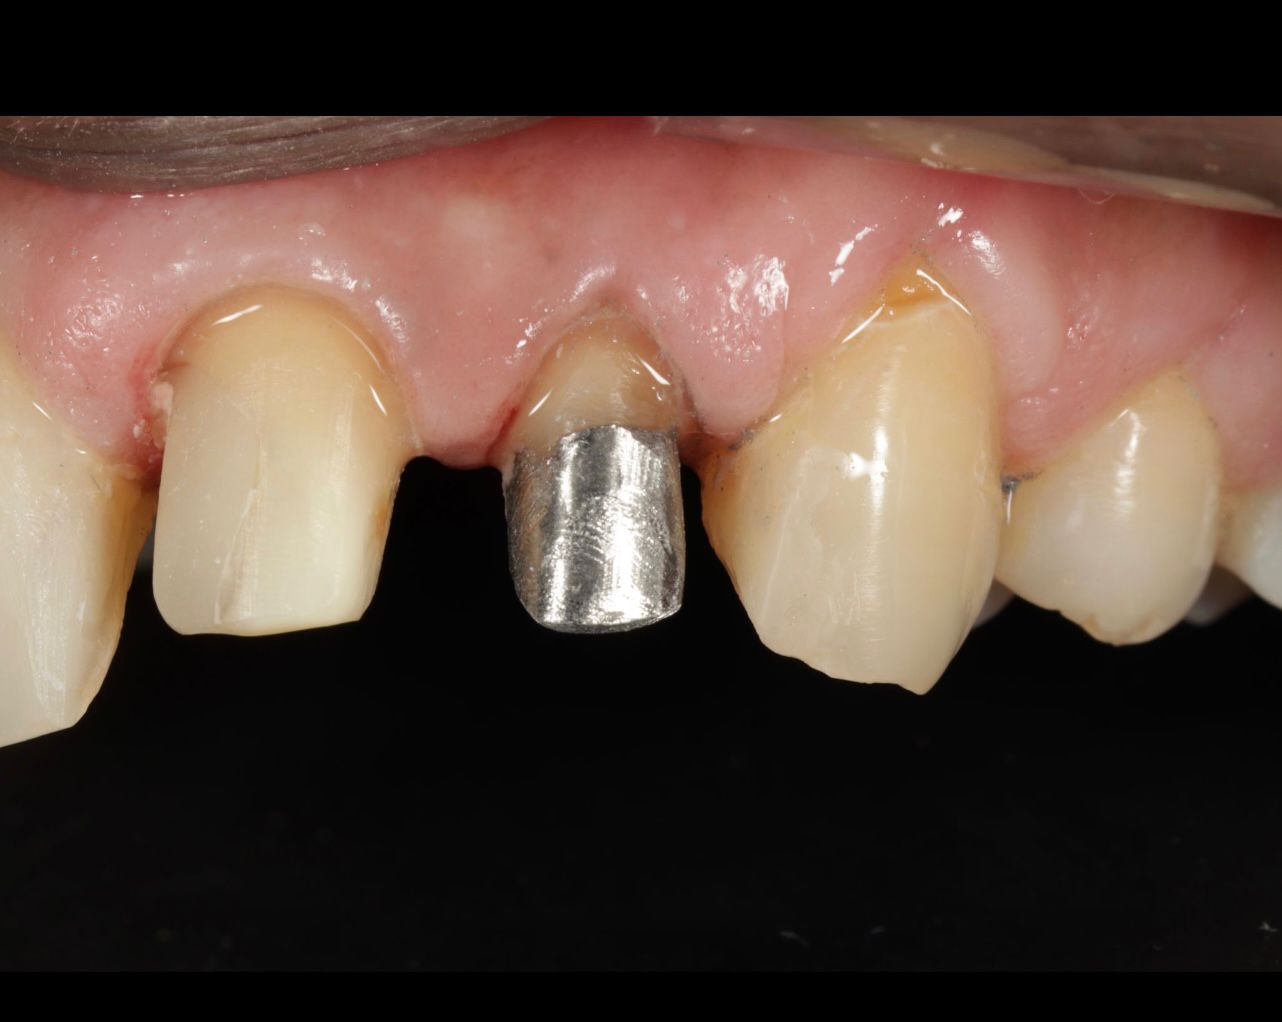

Examination revealed an intraoral sinus tract adjacent to a previously root canal-treated tooth. The tract was non-tender but expressed a small amount of pus on pressure. The existing full-coverage crown appeared intact externally, masking the underlying issue.